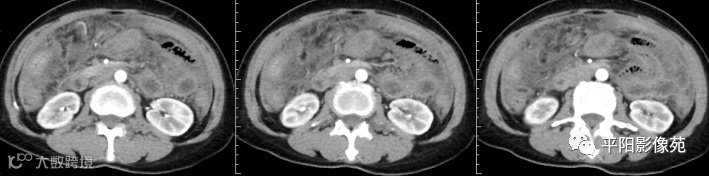

腹部增强 门脉期

壁腹膜增厚伴或不伴腹水;增厚的腹膜光滑、均匀,呈线带状,部分可见腹膜结节,网膜及肠系膜广泛浸润性改变;增强扫描明显强化。

合并淋巴结肿大,可钙化,若中心干酪样坏死,增强扫描环形强化

湿型:渗出性高密度腹水(CT值20-45HU),高密度由于高蛋白和细胞含量多可能。